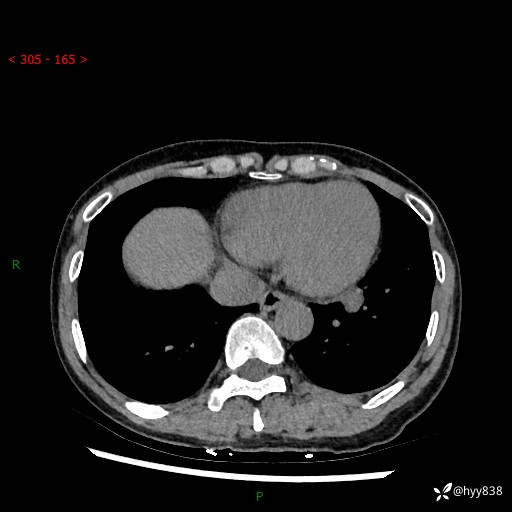

【患者信息】:55岁/女

【主诉】:咳嗽咳痰半月,发现肺占位2天

【现病史及既往史】:患者半月前出现咳嗽咳痰,伴头晕胸闷、无发热气喘。于当地医院住院行抗感染治疗1周(具体药物不详),后咳嗽减轻,但仍未完全缓解,复查胸部CT示:左肺下叶1.8*1.2结节软组织影。为求进一步诊治来我院,门诊以“肺占位”收入院。 自患病以来,精神、饮食、睡眠尚可,大小便正常,体力体重无明显减少。

【检查】:胸部CT平扫+增强

各期CT值:40hu 57hu 49hu